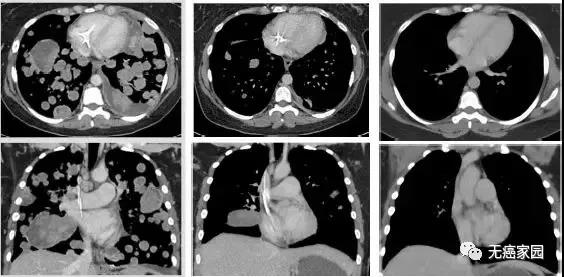

癌症患者因为癌细胞出现扩散转移所以在临床上会出现很多的并发症,患者水肿疼痛也是晚期非常常见的一种症状。引起水肿的原因有很多譬如:低蛋白血症,肿瘤压迫了静脉回流等等...